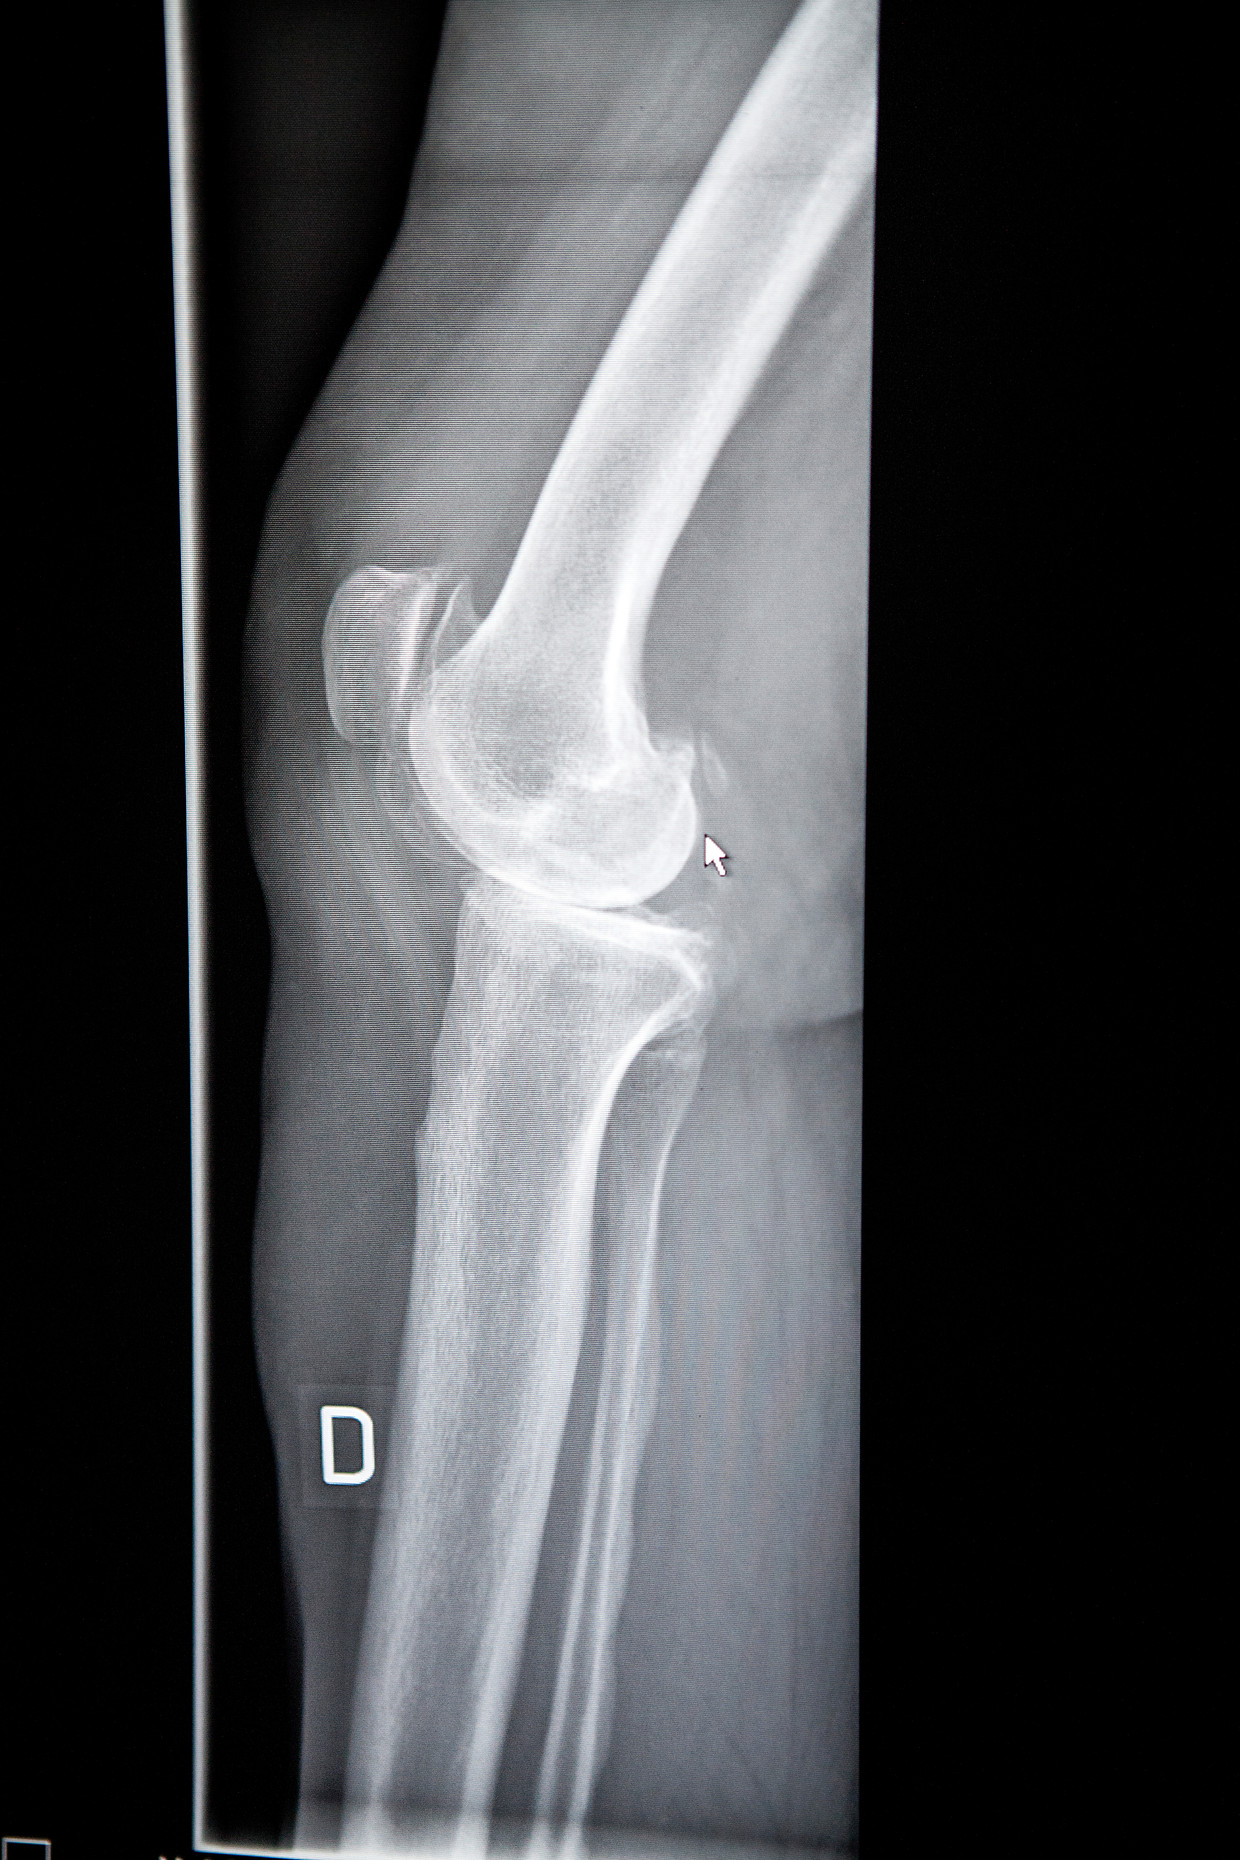

Source: davonteuws.pages.dev De Knie Knie artrose Dokter Hans Frejlach , Met behulp van een röntgenfoto worden afwijking zichtbaar, bijvoorbeeld na een ongeval of operatie Een röntgenfoto kan uiteindelijk een artrose in de knie aantonen: artrose geeft röntgenologisch een versmalling van de gewrichtsspleet.

Source: techeatil.pages.dev Röntgenfoto Van Ernstige Osteoartritis in De Knie Van Een Hond Stock Foto Image of lichaam , Ook kan vastgesteld worden of er sprake is van artrose (slijtage) van de knie Röntgenfoto van de knie Om vast te stellen of er afwijkingen aan uw knie bestaan wordt er zo nodig een röntgenfoto gemaakt

Source: cfaqjfcpb.pages.dev Kniegelenk. Die (MRT) Scan eines seitlichen Blick auf das Kniegelenk , Een röntgenfoto kan uiteindelijk een artrose in de knie aantonen: artrose geeft röntgenologisch een versmalling van de gewrichtsspleet. Een röntgenfoto van de knie geeft een duidelijk beeld over de anatomie van de knieschijf en haar relatie tot de groeve waarin ze spoort

Source: ifesbdzro.pages.dev Poster Een röntgenfoto van een Artritis knie 60x80 cm , Ook geeft de foto een idee van de status van het kraakbeen. Deze plaat is verbonden met een computer en een beeldscherm